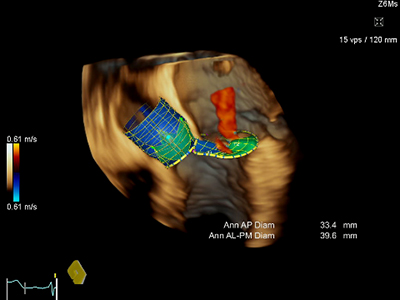

特長<2>

弁の自動解析:eSie Valves

3D経食道プローブで取得したデータからの弁の計測を自動で解析。僧帽弁に加え,大動脈弁まで対応し,画像を選択したら後はワンクリック,わずか5秒程度で解析が完了します。TAVIの人工弁サイズの決定に役立つ計測結果も,その場で瞬時に提供します。